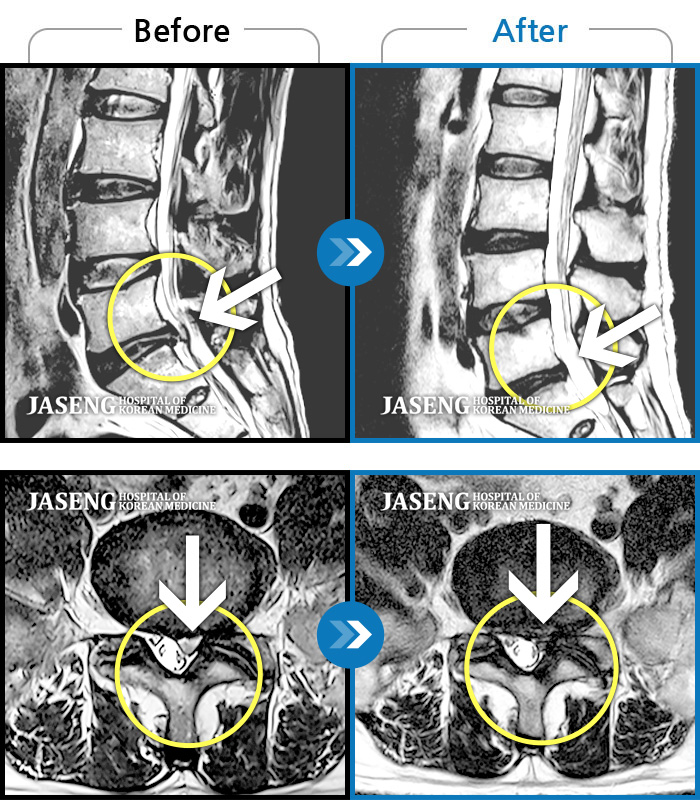

허리디스크

천안 · 김세정 원장

요통 및 다리통증이 매우 심해 움직이기 어려운 상태였습니다.

촬영시기

2023.03.20 ~ 2023.12.26